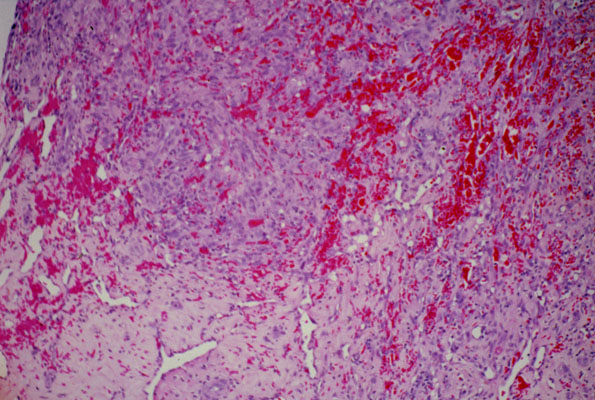

Kaposi sarcoma, histology

The lesion consists of elongated cells which line vascular slit-like spaces and form solid nests. In between these cells, there are numerous extravasated red blood cells. Towards the periphery, the vascular spaces are more dilated.